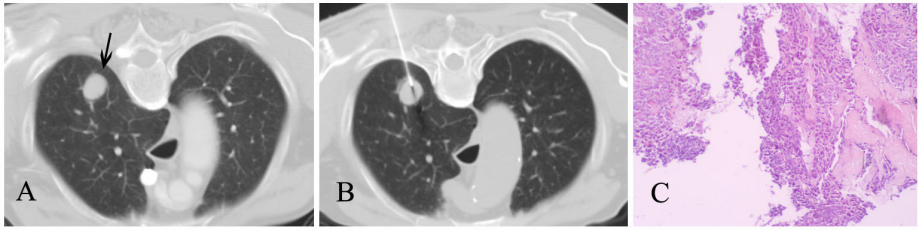

(1)CT引导下肺穿刺活检

图A显示右肺上叶类圆形小结节(箭头),性质难定;图B:在CT引导下行穿刺活检;图C:病理结果证实为小细胞肺癌。